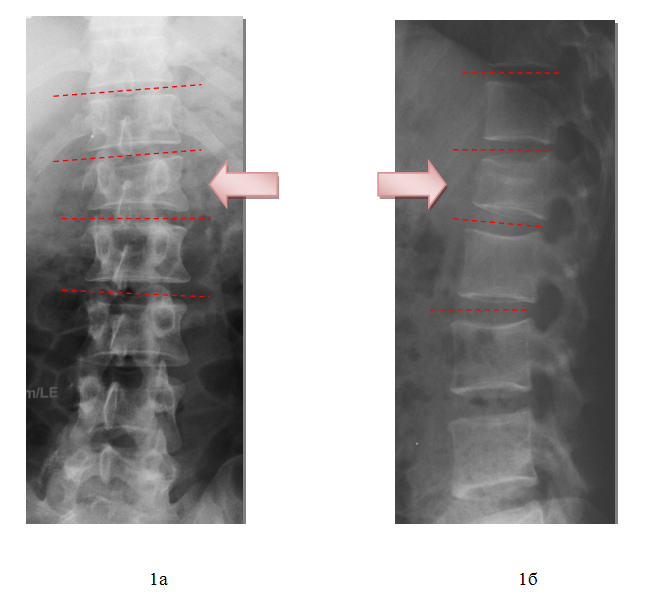

После предоперационной подготовки в кратчайшие сроки пациенту выполнена операция: Задняя внутренняя коррекция и фиксация позвоночника чрескожной транспедикулярной системой «Viper 2 3D» DePuy-Synthes.

В первые сутки после операции больной поднят на ноги, ходит без дополнительных средств опоры. Боль купирована. Пациент абсолютно удовлетворен результатом оперативных вмешательств.